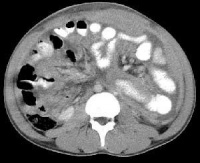

Bk9w2.jpg